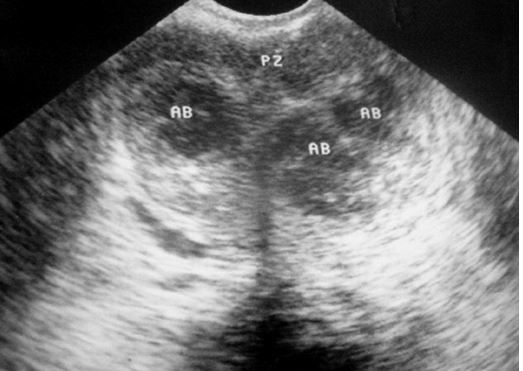

Abscess tuyến tiền liệt là một biến chứng của viêm tuyến tiền liệt cấp do vi khuẩn. Tỷ lệ abscess tuyến tiền liệt hiện nay rất thấp do việc sử dụng kháng sinh thích hợp. Cần nghĩ đến khi bệnh nhân có tiền căn đái tháo đường, HIV hay điều trị kháng sinh ban đầu không đáp ứng sau 48h. Để chẩn đoán xác định cần thực hiện các phương tiện chẩn đoán hình ảnh như siêu âm qua ngã trực tràng và CT scan. Dấu hiệu của abscess trên siêu âm là hình ảnh vùng echo kém. CT scan sẽ cung cấp chính xác vị trí, kích thước ổ abscess để hỗ trợ trong việc lên kế hoạch điều trị cũng như xác định có tổn thương lan rộng ra khỏi tuyến tiền liệt hay không.

Hình 1: hình ảnh các vùng echo kém của abscess tuyến tiền liệt